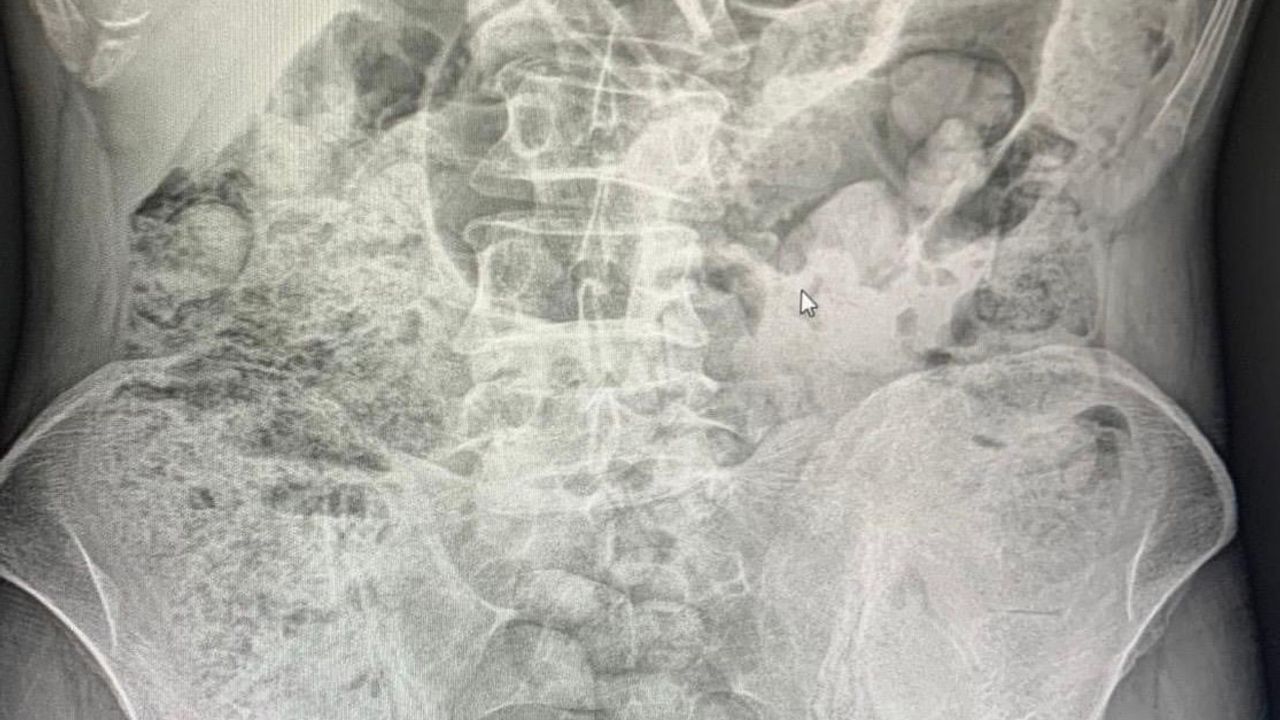

Siirt'te 4 zanlının midesinden çıkarılan 1 kilo 597 gram uyuşturucu madde, 10 gün süren hastane tedavisinin ardından cerrahi müdahale ile elde edildi. Tutuklanan zanlılar arasında 3 İran uyruklu kadın ve 1 erkek bulunuyor.

Siirt Emniyet Müdürlüğü Narkotik Suçlarla Mücadele Şube Müdürlüğü, 14 Aralık'ta Baykan Şehit Bünyamin Torgut Polis Uygulama Noktası'nda durdurduğu iki araçta, uyuşturucu madde taşımak için yutma yöntemini kullanan kişileri yakaladı. Yapılan incelemeler sonrasında, şüpheli şahısların midelerindeki uyuşturucu maddeler, 10 gün süren hastane süreci sonunda cerrahi yöntemle çıkarıldı.

Cerrahi Müdahale ile Elde Edilen Uyuşturucu

Midelerde toplamda 119 paket halinde 1 kilo 597 gram uyuşturucu madde tespit edildi. Zanlılar, çıkarıldıkları adli makamlarca tutuklanarak cezaevine gönderildi.

SİİRT’TE 4 ZANLININ MİDELERİNDEKİ 1 KİLO 597 GRAM UYUŞTURUCU MADDE, 10 GÜNLÜK HASTANE SÜRECİNİN ARDINDAN CERRAHİ MÜDAHALEYLE ÇIKARTILDIKTAN SONRA TUTUKLANDI.